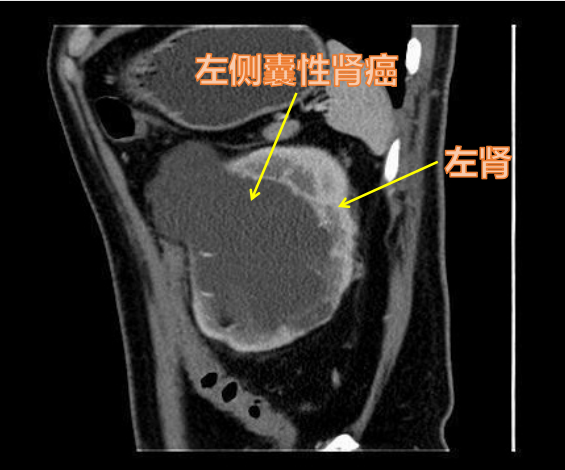

我的邻居许先生今年45岁,三年前体检B超无意中发现双侧肾脏各有一个囊性占位(左侧最大径2 cm,右侧最大径3 cm),当时超声考虑是单纯性肾囊肿,他也没有啥不舒服,后来一直也没有复查。直到两周前的一天清晨,他起床后上厕所发现自己肉眼血尿,并有左侧腰部酸胀不舒服,马上去附近医院就诊。医生给他复查了泌尿系统彩超,结果显示双侧肾囊肿都变大了,更要命的,左肾"囊肿"似乎并不是"单纯性",增强CT给出的答案是:高度怀疑囊性肾癌,Bosniak Ⅳ级。

囊性肾癌在肾细胞癌中约占4%~15%,多发生于男性病人,肿瘤细胞来源于肾小管的上皮细胞,以囊肿的形式呈膨胀性生长,慢慢形成一个或者多个大小不一的单房或多房囊性肾癌。它的临床症状和表现包括患侧腰部疼痛、肉眼或显微镜下血尿、腹部包块、食欲不振、消瘦、反复低热等。有时候通过B超检查,难以区分囊性肾癌与单纯性肾囊肿,常常需要高分辨率的增强CT扫描才能够进一步辨别。

囊性肾癌周围分界不清晰!